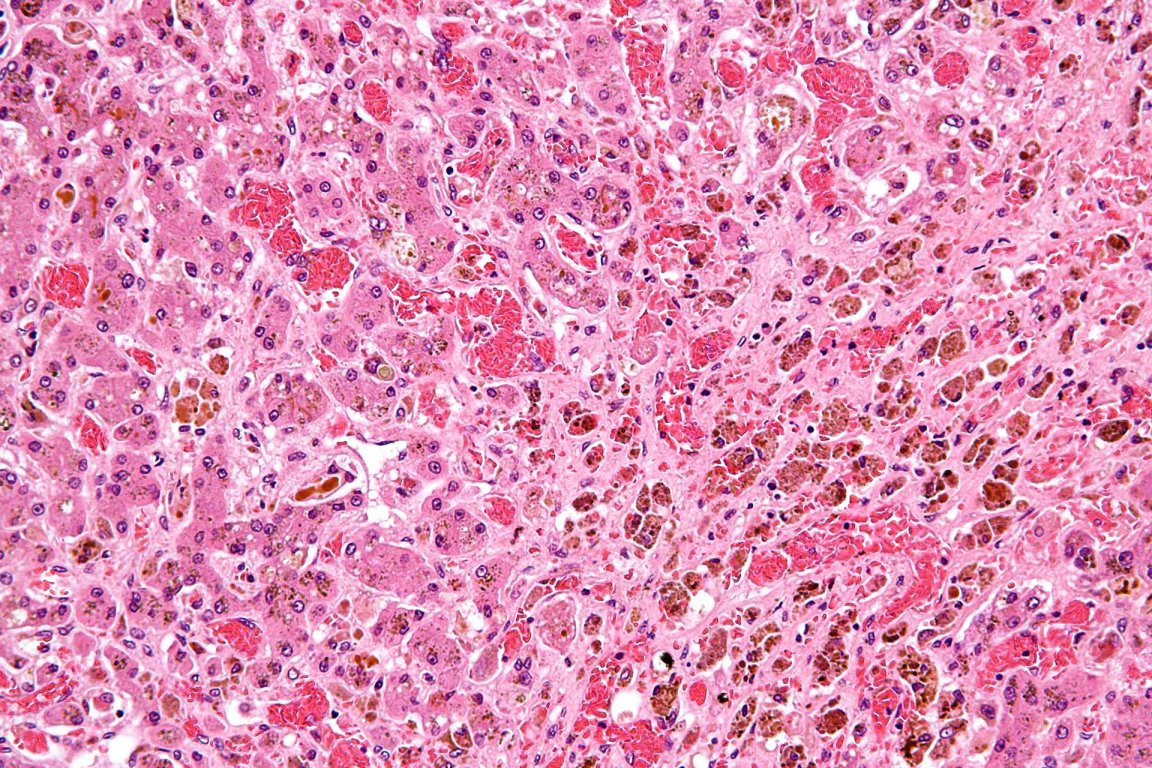

Excess intake of alcohol and other diseases damage a liver’s healthy cells, known as hepatocytes. The gaps left by the damaged cells are filled by myofibroblasts that generate scar tissue in the liver. Because the liver can’t generate hepatocytes fast enough to combat the scar tissue, the liver begins to fail.

Results of the trial showed an increase in the number of healthy cells and collagen content in the livers of the mice.